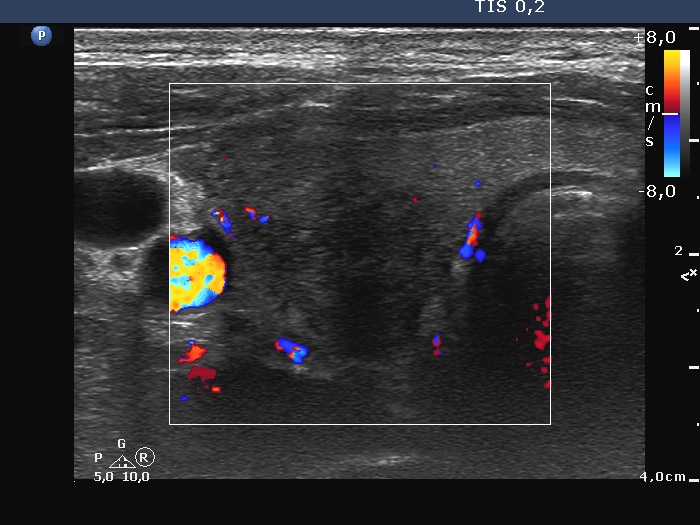

Right lobe, longitudinal scan

Right lobe, transverse view, color Doppler mode. The vascularity is absent in the hypoechoic areas.